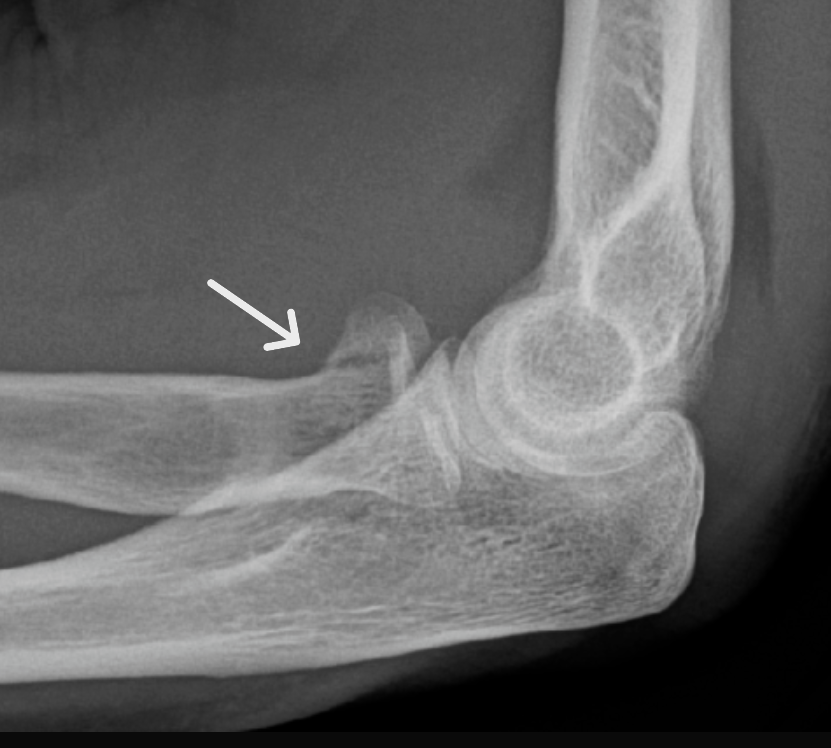

여러 각도에서 촬영한 X-레이 검사가 기본이며, 요골두 골절은 골절선이 잘 보이지 않는 경우도 있어 진단이 어려울 수 있습니다.

관절 내 체액 증가(혈종) 등이 X-레이에 간접적으로 나타날 수 있습니다.

정확한 평가가 필요한 경우 CT나 MRI 검사로 골절 상태와 주변 인대, 힘줄 손상 여부를 확인합니다.